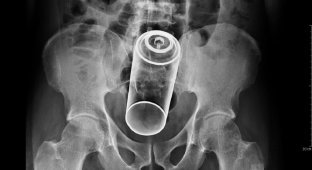

Эксперты составили рейтинг вещей, которые застревали в разных отверстиях людей в 2025 году (5 фото)

Медики поделились списком предметов, которые «случайно» застревали в разных отверстиях любителей острых ощущений в прошлом году. Ниже перечень предметов с указанием отверстий, из которых их достали.

Все случаи — реальные отчёты из базы Комиссии по безопасности потребительских товаров, куда поступают анонимные данные о визитах в отделения неотложной помощи.

Прямая кишка:

— Фонарик на батарейках;

— Фонарик;